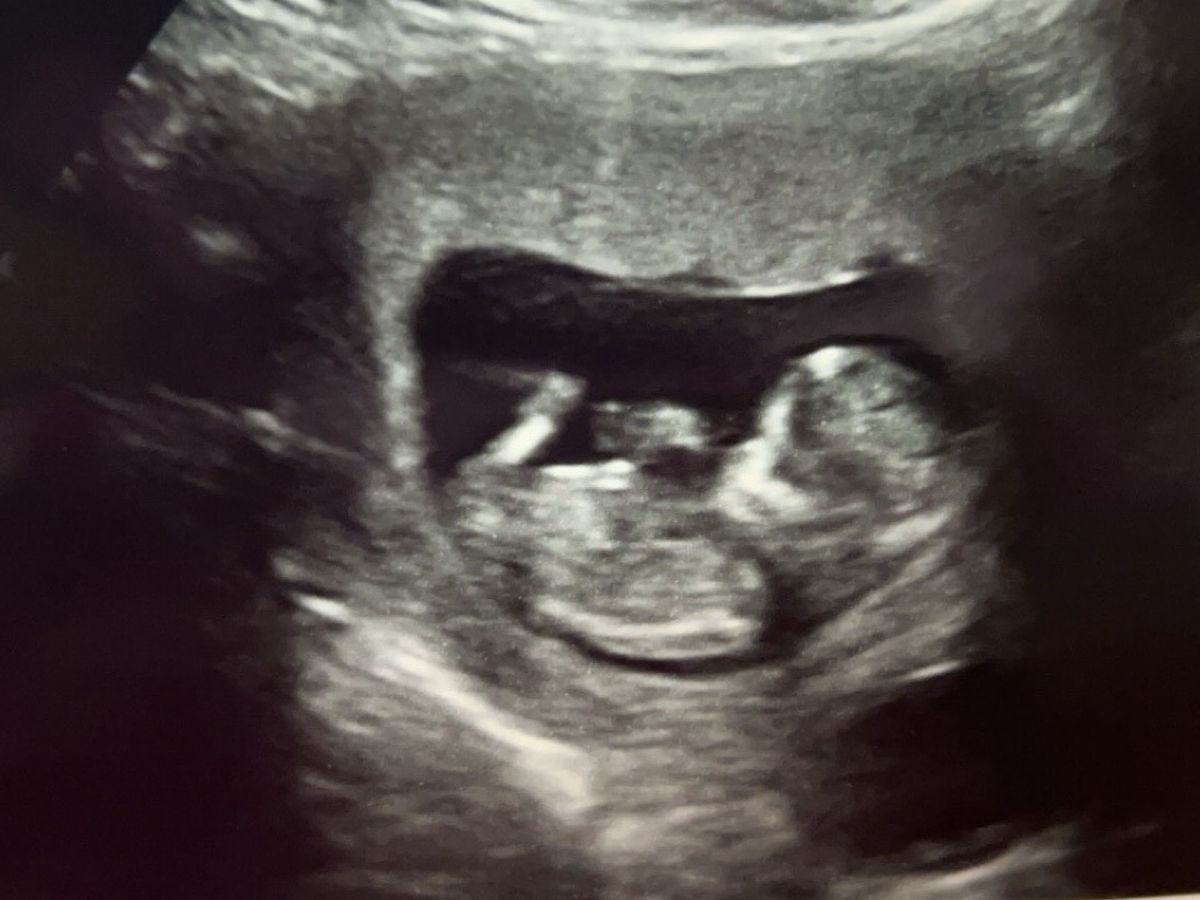

i don’t even know where to start just putting my pride aside and asking for a little help. Most know I’m 24 weeks pregnant high risk. I have missed a lot of work since July with er visits, regular visits and specialist appointments. Now my sugars are out of control and have to have more visit an ekg. No car since July things just been low hit after low hit. So funds have been low as is and if that’s not low enough I’m getting hit with a garnishment that I tried to work outside of court. I just need a little help getting caught up before Azylah comes. Anything helps. Thank you and god bless